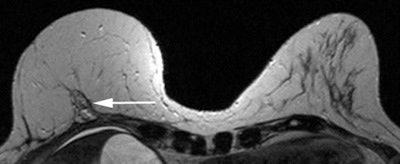

Reconstruction with latissimus dorsi myocutaneous flap: Latissimus dorsi muscle, fat and skin are rotated to reconstruct the breast. Top: Sagittal fat-saturated T1-weighted image shows latissimus dorsi muscle flipped anteriorly for reconstruction (white arrows) and the denuded dermal layer is seen parallel to the chest wall (white arrow heads). Bottom: Axial fat-saturated T1-weighted subtraction image with postcontrast gadolinium injection, the flap consisting of the latissimus dorsi muscle and its overlying skin and fat flipped and tunneled from the back to the neobreast (white arrow), giving a tailed appearance to the muscle in the lateral breast. This can be used as a differentiator on imaging from transverse rectus abdominis myocutaneous (TRAM) flap reconstruction. All images courtesy of Dr. Vandana Dialani.